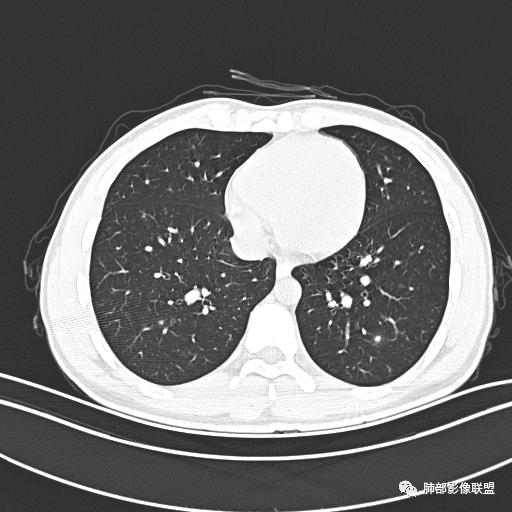

男,19岁

主  诉:发热、全身皮疹2天。

现病史:患者源于2天前受凉后出现发热,最高体温为38.5℃,且颜面部出现少量皮疹,无鼻塞、流涕、咳嗽、咳痰,未在意而未作特殊处理,次日全身皮疹逐渐增多至全身,伴轻度瘙痒,在当地卫生所给予抗病毒、抗感染治疗(具体用药不详)体温有所下降,但皮疹无明显消退,无腹痛、头痛,食欲无明显减退,为进一步诊治,遂于今日急来我院求治,患者目前精神尚可,体力正常,食欲正常,睡眠正常,体重无明显变化,大便正常,排尿正常。

小强:青年,发热,皮疹;双肺散在结节,周围磨玻璃,点晕征,疱疹病毒感染,鉴别荚膜组织胞浆菌,结核。 大雄:青年,急性起病,发热伴全身皮疹2天,抗病毒治疗体温有下降。双肺随机分布大小不等类圆结节,“点晕征”。考虑水痘-疱疹病毒(VZV)血播询问接触史,查体皮疹分布以及形态基本可诊断。 王开金江津中心医院呼吸科:青年男性,起病急,病程短,以发热,皮疹为首发症状,感染指标以单核细胞升高为主,胸部ct双肺多发结界,周围有晕,点晕表现,随机分布,同意於老师意见,水痘疱疹病毒血流感染累及肺。 王秀仙:双肺多发大小不等结节,周围有晕,边缘模糊,呈点晕征表现。青年,急性起病,发热伴全身皮疹2天,抗病毒治疗体温有下降。考虑疱疹病毒。鉴别荚膜组织胞浆菌。 傅昌瑜:19岁男性,发热、全身皮疹2天,单核细胞增高,双肺多发结节,结节边缘见边界不清磨玻璃影。点晕征+发热、全身皮疹+单核细胞增高——考虑水痘-带状疱疹病毒肺炎。 一切∮随缘:年轻男性,发热,皮疹两天,实验室,CRP,PCT增高,影像:双肺多发散在磨玻璃结节,边界欠清,大小不等,呈点晕征改变,以血管束周围分布为主,局部血管束略增粗,其它无明显改变,考虑:1:病毒性肺炎(水痘疱疹病毒?不知道皮肤有无改变)2:真菌(组织胞浆菌,血管侵袭性肺曲霉)3:GPA4:寄生虫(实验室没有看到嗜酸细胞增高) 赵山河:双肺散在结节,周围有晕,边缘模糊,呈点晕征表现。青年,急性起病,发热伴全身皮疹2天,抗病毒治疗体温有下降。考虑水痘—疱疹病毒感染。洪桥爱:青年男性,发热、皮疹2天,伴瘙痒,皮疹于面部首发,之后进展至全身,虽然没有对皮疹进行描述,但是从出疹时间及皮疹进展情况,伴瘙痒,应该就是个水痘患者;CT提示双肺随机分布结节影,部分结节伴有边界不清晕征,考虑水痘血播肺。 刘强:年轻男性,急性起病,皮疹,发热,抗感染治疗体温下降,说明有效。影像表现为散在点晕征,感染类疾病谱(疱疹病毒,真菌,结核),结合年龄,皮肤皮疹,考虑水痘-疱疹病毒性肺炎。 小兜:男性,19岁,发热皮疹两天,颜面部至全身,CRP,降钙素及单核增高。CT示双肺散在小结节,周围伴磨玻璃影,点晕征,考虑为水痘-带状疱疹病毒(varicella-zoster virus,VZV)肺炎 必有路:青年,皮疹+发热+“点晕征”→水痘-疱疹病毒(VZV) 许慧良:青年男性患者,发热、皮疹2天,体温最高38.5℃,第3天皮疹扩展至全身,伴瘙痒,胸部CT:双肺多发随机分布的小结节,结节周边见边界模糊的晕征,考虑水痘病毒感染流心明智:男,19,急性起病,发热伴全身皮疹2天。出疹顺序头→全身,抗病毒有效。胸部CT:两肺多发大小不等类圆形实性小结节影,随机分布,结节周围环绕GGO,边界模糊,呈点晕征。出疹特点是关键,未提示。考虑:血播病毒性肺炎,水痘-疱疹病毒?麻疹?鉴别荚膜组织胞浆菌、TB、血管炎、寄生虫等。 浪迹天涯:病灶多为5-10mm大小结节,结节周围可见磨玻璃样的晕环,常多发,可分布于肺内任何区域,考虑水痘—带状疱疹病肺炎如果短时间内有新的一个区域浸润,更加能说明,